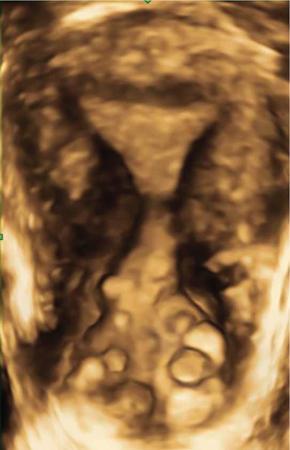

VAGINAL CYSTS Sumeena The vagina is a fibromuscular sheath. Vagina extends from uterus to the vulvar vestibule. The vagina is located in the middle compartment of the pelvis and it is related anteriorly to bladder and urethra, posteriorly to lower rectum and anal canal. The length of vagina ranges from 4 to 12 cm. The posterior wall of vagina is longer and it ends in posterior fornix; the anterior wall is shorter and ends in the anterior fornix. The wall of vagina is composed of three layers: (a) The mucosa consists of nonkeratinized stratified squamous epithelium without glands and its hormone sensitive layer; (b) the muscularis made up of connective tissues and smooth muscle; and (c) the adventitia, which is fascia that connects the vagina to the surrounding pelvic structures and maintains support. The prevalence of vaginal cysts is estimated to be less than 1%. They typically present in the age of 30–40s. Their origin may be Müllerian, Wolffian, squamous or urogenital. Risk factors for vaginal cysts: The vagina may be underevaluated due to probe positioning in routine pelvic US and due to poor vaginal tissue characterization in CT examinations. Though MR imaging provides good tissue characterization, we must focus on the vaginal region to identify any incidental findings. The strengths and limitations of each imaging modality must be understood in assessing the vagina. US is the first-line imaging modality since it is readily available, cost-effective, high resolution and no ionizing radiation. Limitations include operator dependence and patient obesity. The major limitation with transabdominal approach is that the upper portion of the vagina is seen well; the inferior aspect of the vagina is obscured due to shadowing from the pubic symphysis. Limitation with transvaginal US is that the transducer is typically placed in the anterior or posterior fornix which bypasses the perineum and vagina. US imaging needs methodic evaluation performed from introitus to the fornices and include transabdominal, transvaginal and translabial approaches. Due to the poor vaginal tissue characterization and ionizing radiation, CT is usually not indicated for evaluation of the female pelvis. When US is inconclusive, pelvic MR imaging is recommended. The vaginal wall anatomy is best imaged with T2-weighted sequences. The vaginal mucosa has high signal intensity, circular and longitudinal muscle layers have intermediate signal intensity. Embryonic Traumatic Epithelial inclusion cyst/epidermal inclusion cyst/squamous inclusion cyst Skene’s duct cysts Urethral diverticulum Infective Filariasis Vaginitis emphysematosa Epidermoid cyst Sebeceous cyst Endometriotic cyst Ciliated cyst Paraurethral mass Rare Lymphangioma Postradiation Haematocolpos Rectocele and cystocele Prolapsed ectopic ureterocele Large nabothian cyst, tunnel cluster cysts Adenoma malignum Most common type of vaginal cysts, almost up to 40% of cystic masses. As Müllerian epithelial tissue can present anywhere in the vaginal wall, the cysts can also be found anywhere within the vaginal walls. Most common location is along the anterolateral aspect of the vagina. Müllerian cysts present as small, midline cystic masses, with no symptoms and require no treatment. Symptomatic vaginal cysts are treated by excision. The entire cyst wall must be removed to prevent recurrence. Adenocarcinoma can arise in a Müllerian vaginal cyst. The epithelium of Gartner’s cysts is devoid of cytoplasmic mucicarmine and PAS-positive material, in contrast to the epithelium of Müllerian cysts. MRI – Gold standard. Mucus secretion is a unique feature of Müllerian cysts and shows heterogeneous T2 signal. Extent of the cyst, surrounding structures are better evaluated in MRI prior to surgery. Incomplete regression of Wolffian ducts leads to the development of Gartner duct cysts. They are usually noted in the upper anterolateral wall of the vagina above the inferior border of the pubic symphysis. Typically less than 2 cm. When these cysts are large enough, they can compress the urethra causing urinary symptoms. It can also be associated with abnormalities of the metanephric urinary system such as an ectopic ureter, unilateral renal agenesis and renal hypoplasia. USG: Anechoic structure in the upper vagina; transvaginal US provides better differentiation than the transabdominal approach. Fig. 11.19.1.1; T2-axial image shows hyperintense cystic lesions, one in posterior fornix and another one in anterior aspect of upper vagina. Both the lesions are above the level of pubic symphysis. Fig. 11.19.1.2; T2-sagittal image shows hyperintense cystic lesions, one in posterior fornix and another one in anterior aspect of upper vagina. Both the lesions are above the level of pubic symphysis. Bartholin glands are commonly located posterolateral to the vaginal introitus and medial to the labia minora. The obstruction of the gland’s duct either by a stone or a stenosis, which may be caused by prior infection or trauma, leads to Bartholin gland cysts. Cysts are typically round and unilocular, seen at or below the level of the pubic symphysis, usually asymptomatic. This is most apparent on coronal plane imaging. USG: Bartholin gland cysts can be imaged by a transperineal approach. Although these cysts are usually asymptomatic, occasional infection may necessitate drainage of the cysts (Fig. 11.19.1.3). Bartholin gland duct can be obstructed due to stone or stenosis, later which can become infected. The Bartholin’s gland abscess size ranges from 2 to 8 cm with an average of 3 to 4 cm. Antibiotics with or without surgical drainage is the treatment. Marsupialization may be needed in recurrent conditions. USG-complex cystic hypoechoic to anechoic lesions increased throughout transmission. Colour Doppler may show peripheral hyperaemia. Spectral flow – low resistance arterial flow. MRI-T2: Tends to show heterogeneous signal T1 C+ (Gd): pericystic enhancement may be seen (Fig. 11.19.1.4). Vaginal inclusion cysts – also known as epidermal inclusion cysts, most commonly are seen in the distal posterior or lateral vaginal wall at sites of previous trauma or surgery. Inclusion cysts are lined by a stratified squamous epithelium and contain keratinous material. Symptomatic cyst needs treatment. The treatment of choice for symptomatic cysts is marsupialization. MRI-DWI shows restriction (Fig. 11.19.1.5). Skene glands are paired structures in periurethral location near external urethral meatus with ducts draining into the urethra. Skene gland cysts can cause UTI or urethral obstruction. They are distinguished from urethral diverticulum, which are usually midurethral. In T2-weighted images, Skene duct cysts seen as round or oval hyperintense lesions just lateral to the external urethral meatus. MRI:T1 hyperintense due to proteinaceous material. T2 hyperintense. Fluid–fluid level if complicated with debris or haemorrhage (Fig. 11.19.1.6). It may be congenital or result from infection or obstruction. In females, diverticula commonly extends from the posterolateral wall of the mid-portion of the urethra. During voiding cystourethrography (VCUG), they are seen best on postvoid images. Transrectal US shows a cystic mass in proximity to the urethra and it will be seen anterior to the vagina. Lack of radiation and capacity to differentiate solid from cystic masses is the advantage of US over CT. CT shows a periurethral lesion with low attenuation. MRI shows T1 hypointense and T2 hyperintense fluid signal intensity. Postcontrast imaging with gadolinium is used to evaluate infection or inflammation. Adenoma malignum of the cervix is a rare variant of cervical mucinous adenocarcinoma. VAGINAL MALIGNANCIES Rupa Renganathan, Suchana Kushvaha The primary vaginal carcinoma is a very rare gynaecological malignancy and accounts for 2%–3% of genital tract malignancies and 10% of all vaginal malignancies. It is defined as a cancer found in the vagina without histological or clinical evidence of cervical or vulvar malignancy and without previous history of treatment of cancers in the last five years. The commonest primary carcinoma is squamous carcinoma, and other rare primaries are adenocarcinoma, melanoma and sarcomas. The secondaries in the vagina are much more common than the primary and account for more than 80% of vaginal malignancies. Primary vaginal carcinoma is common in elderly, however, seen in the younger women when associated with human papillomavirus (HPV 16 and 18). Vaginal carcinomas are staged based on FIGO classification. Management of the cancer is usually based on the stage of the disease and the histological subtypes. Vagina is an elongated fibromuscular structure connecting the uterus with the vulva. It is approximately 7–9 cm long. The long axis is oriented 90 degrees to the uterine axis and its upper part is oriented almost horizontally and in plane with the pelvic floor. It is lined by the nonkeratinizing stratified squamous epithelium. It has anterior, posterior and lateral walls. The upper portion of vagina is invaginated by the cervix such that a space is created between its walls and the cervix called fornices. The posterior fornix is deeper than the anterior fornix. Anterior wall is separated from the bladder base and the urethra by the anterior vesicovaginal septum while the posterior wall is separated from the rectum by rectovaginal septum. The posterior fornix is covered with the peritoneal reflection that forms the Pouch of Douglas. It is supplied by the vaginal arteries, originating from the internal iliac artery and branches of uterine, middle rectal and inferior vesical arteries. There is considerable overlap in the lymphatics between the various parts of vagina. The upper two-thirds of the vagina drain into the pelvic lymph nodes that include external, internal and common iliac groups and the lower third into the superficial inguinal and femoral lymph nodes. The posterior vaginal wall also drains into the perirectal lymph nodes. MRI is the standard imaging modality for local staging of cancers and also for assessment of treatment response and surveillance due to superior soft tissue resolution, multiplanar capability. In a relaxed state, it is seen as a ‘H’ shaped structure posterior to urethra with the anterior and posterior walls being opposed to each other. The vaginal lumen may have secretions or blood-causing distention of its lumen. The anatomy of the vagina is best depicted on T2w images where three layers of its wall can be distinguished in a nondistended state. The mucosa is T2 hyperintense with a hypointense submucosal and muscularis layer beneath it. It is surrounded by adventitia which is hyperintense due to the venous plexus (Fig. 11.19.2.1A and B). For accurate staging purposes, vagina should be distended with ultrasound gel with the help of a syringe and infant feeding tube (Fig. 11.19.2.1C and D). Before inserting gel, patient consent must be taken and her marital status should be enquired. Care must be taken that air is not insufflated while introducing the jelly. Jelly can also be introduced in patients other than carcinoma vagina in cases where vaginal involvement is suspected in other malignancies. After adequate distention, the walls get separated and the fornices are better delineated. For staging purposes, the vagina is divided into three parts. The upper one-third lies above the level of the bladder base and includes the fornices. The middle one-third is opposite to the bladder base and the lower one-third opposite to the urethra (Fig. 11.19.2.1D). Ultrasound owing to its limited field of view and inaccurate staging is not used for imaging of vaginal pathologies. CT has poor contrast resolution and is used only for lymph nodes staging in known patients of vaginal malignancy. PET CT has the advantage in that it combines both the functional and anatomical information about the tumour. While performing PET for the gynaecological malignancies, general measures to reduce bladder activity, like Foley’s catheterization, IV hydration and diuretic administration, are adapted and the image acquisition is done from the pelvis cranially. The advantage of PET beyond providing functional information is that it provides information about distant metastases. The presence of nodal metastases in patients with vaginal cancers portends a poor prognosis and alters the management. In a study by Christensen et al., PET CT was found to be more sensitive and carried greater negative predictive value as compared to MRI for detection of lymph nodes. However, commonly seen inflammatory and the reactive lymph nodes may show uptake. Node biopsy or excision is mandatory wherever the metastatic involvement is indeterminate or questionable. PET CT is recommended for restaging the recurrent tumour, and differentiating the treatment changes from recurrence in vaginal carcinomas. In cases of vaginal sarcomas, it is used for grading, staging and follow-up imaging. MRI is the main investigation for evaluation of vaginal masses and for both staging and surveillance. Patients are requested to be fasting for at least 4 hours to limit bowel motility and to empty the bladder 1 hour before the study to achieve moderate distention of the bladder. Use of antispasmodic agents like Butylscopolamine 40 mg IM/IV or Glucagon 0.5–1 mg IV/IM can also be considered to reduce bowel movements. The vagina should be distended with about 60 mL of Ultrasound Gel for evaluation of vaginal lesions. The patient is imaged in supine position with phased array abdomino pelvic coil. The saturation band is usually placed anterior and superior to the field of view. T2 imaging remains the mainstay for evaluation of vaginal tumours. The basic sequences for evaluation of vagina lesions are T2 sagittal, axial, coronal and oblique axial, T1 axial and diffusion-weighted imaging in axial plane. The high-resolution oblique axial along the plane of vagina is the best sequence which demonstrates the tumour and its extent. The study may be completed by contrast injection. The sequences for contrast evaluation will include pre-T1 with fat saturation, followed by dynamic contrast injection and postcontrast T1 fat saturated acquisition. The most common clinical presentation would be painless vaginal bleeding (65%–80%) followed by vaginal discharge, pelvic pain, urinary symptoms and mass being felt in the vagina. The primary carcinoma are usually squamous cell carcinoma and accounts for about 80% of cases. They are more commonly seen in the upper third in the posterior wall. It is associated with HPV and about 30% of women also have history or associated intraepithelial and invasive cancers of cervix and vulva. About a third of patients present with lymph nodal metastasis in the pelvis or inguinal region at the time of clinical presentation. Adenocarcinoma accounts for only 9% of primary vaginal malignancies, and they are usually seen in the anterior wall of the upper third of the vagina. They affect younger age group (14–21 years) and arise from the lesions such as endometrial deposits and the vaginal adenosis. About two-thirds of the cases have exposure to Diethylstilbestrol to their mothers. When seen in older women, they are usually clear cell carcinomas. Staging of vaginal carcinoma with MRI parallels clinical FIGO staging (Figs 11.19.2.2–11.19.2.4). The tumour is best seen on T2-weighted sequences where it is seen as an intermediate signal (higher than muscle and lower than fat). Adenocarcinomas typically exhibit high T2 signal. Because of the signal on T2, the tumour is well delineated from the vaginal wall which displays low signal intensity. When the tumour is limited to vagina, it is difficult to be seen on T1 sequences unless it causes a contour abnormality as the tumour will be isointense on T1. Stage I tumours are those which are either seen as mass/plaque like thickening but will be limited to vagina and will be diagnosed if the hypointense T2 signal of the vaginal wall is preserved (Fig. 11.19.2.5). When the tumour disrupts this hypointense layer and extends into the paravaginal fat, the staging becomes Stage II (Fig. 11.19.2.6). The loss of normal signal of the vaginal wall should be looked at all three orthogonal planes to identify subtle loss of the signal which is the important finding which upstages the tumour.